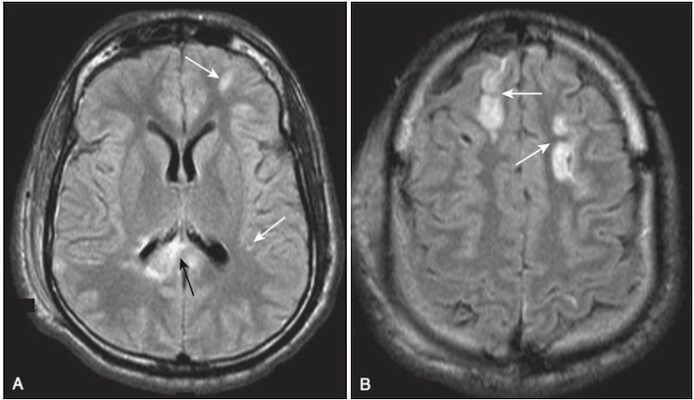

- MRI là nghiên cứu được lựa chọn trong việc xác định tổn thương sợi trục lan tỏa.

- Các chấm xuất huyết nhỏ có thể sáng trên hình ảnh T1w. (Trên một số chuỗi quét mới hơn, những chấm xuất huyết này có thể có màu sẫm.)

- Phát hiện thường gặp nhất là nhiều vùng sáng trên ảnh T2W tại điểm nối vỏ-tuỷ ở thuỳ thái dương hoặc thuỳ đỉnh hoặc trong thể chai (Hình 13).